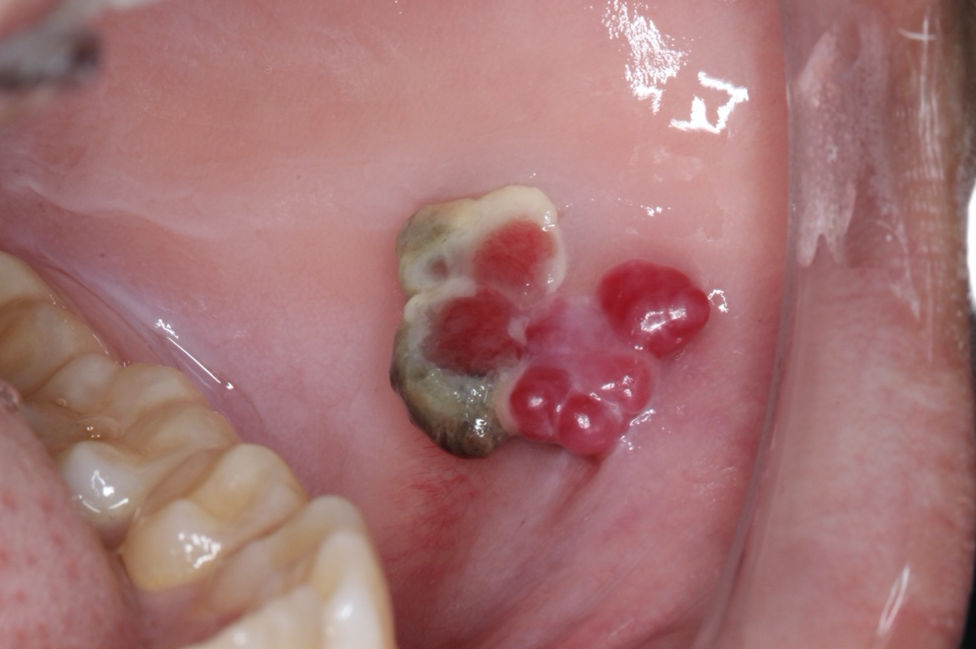

65-year-old woman with oral lesion

A 65-year-old woman presented with an oral lesion on the left posterior mandible that was noted on a panoramic film.